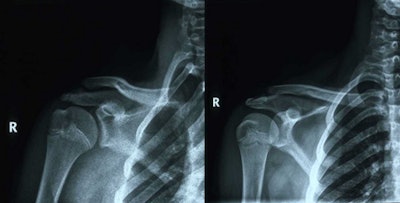

Radiographs were performed either on a digital radiography (DR) system or a computed radiography (CR) system. Image processing or enhancement was applied on DR images and CR images depending on requirement.

Ultrasound was performed using a 5- to 13-MHz linear probe, but in large patients a lower frequency probe of 2 MHz to 6 MHz was necessary. CT was done on a four-slice spiral scanner, and MRI was performed in sagittal, coronal, and axial planes. In all patients, T1- and T2-weighted images were obtained. In addition, T1-weighted gradient-recalled echo (GRE), T2-weighted fast spin-echo (FSE), T2-weighted fat-suppressed, and other sequences, such as proton density-weighted and proton density-weighted fat-suppressed, were done as and when required.

All investigations were performed by a radiologist with 11 years of experience as a general radiologist and one year as a musculoskeletal radiologist. Radiographs were performed in cases of suspected fractures, followed by a CT scan if the diagnosis was in doubt. Ultrasound was performed in all cases of suspected soft-tissue injuries, followed by MRI for further characterization in cases of clinical indication. CT also was performed in cases of suspected osseous injury.

After knee injuries, injuries to the shoulder were the most common. A total of 30 wrestlers sustained 35 shoulder injuries (18.6%). The mean age was 18.8 ± 3.22 (range 12 to 27 years), the mean weight was 68.96 kg ± 12.93 (range 42 to 94 kg), and the mean height was 168.33 cm ± 11.225 (range 132.5 to 187.5 cm). Total athlete exposure was 9,743, meaning the injury rate was 3.59, the case rate was 1.16, and the player rate was 0.15.